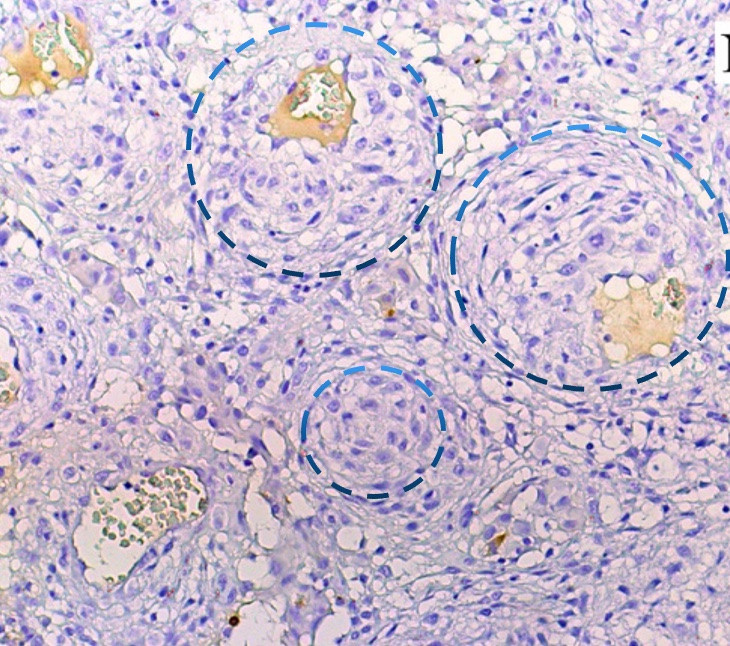

Разметка трансформированных клеток плеоморфных ксантоастроцитом

Окраска: гематоксилин и эозин. Увеличение х 200